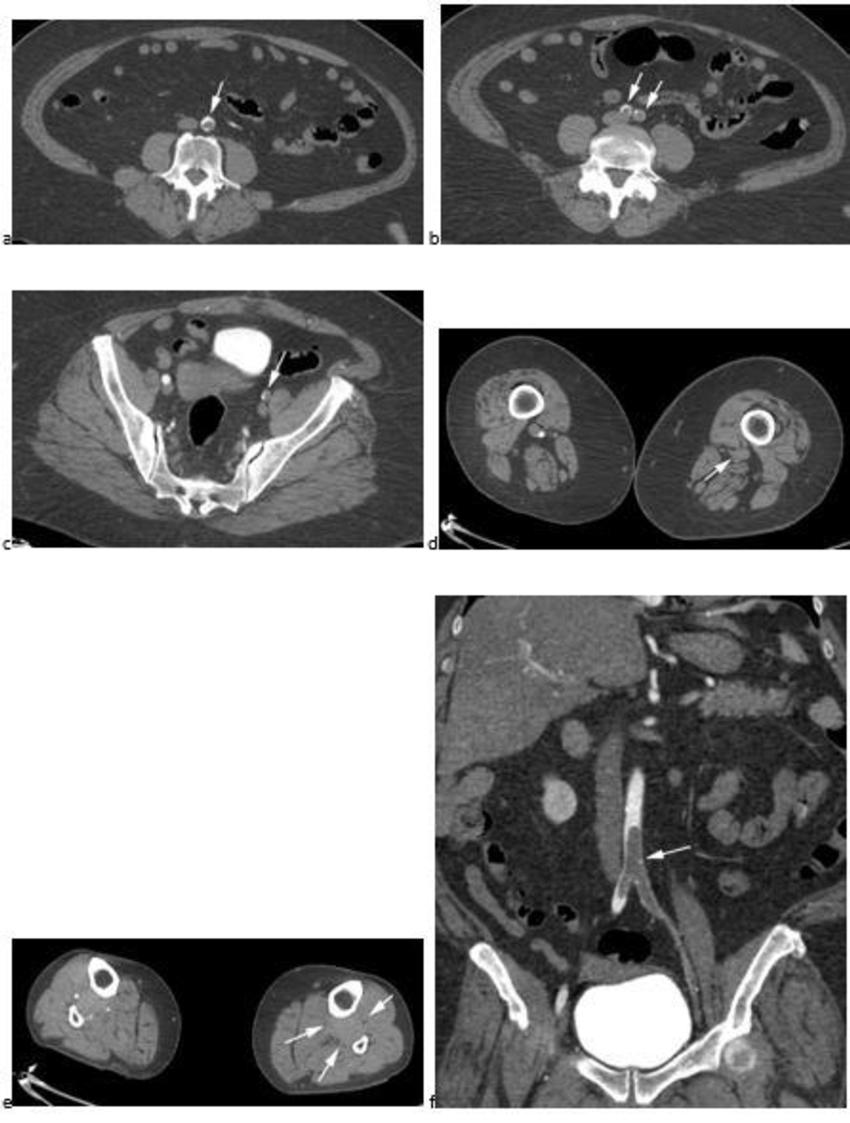

Figure 2. CTA images from a 63-year-old woman with COVID-19. Images through the (a) distal abdominal aorta, (b) proximal common iliac arteries, (c) external iliac arteries, (d) popliteal arteries, and (e) anterior tibial, posterior tibial, and peroneal arteries demonstrate lack of contrast opacification on the left (arrows). Hyperdensity along the periphery of the vessels in a and b corresponds to contrast rather than calcium. Note that the arrows in e point to the expected location of the vessels. (f) Oblique coronal reformatted CT image demonstrates clot at the aortic bifurcation (arrow).